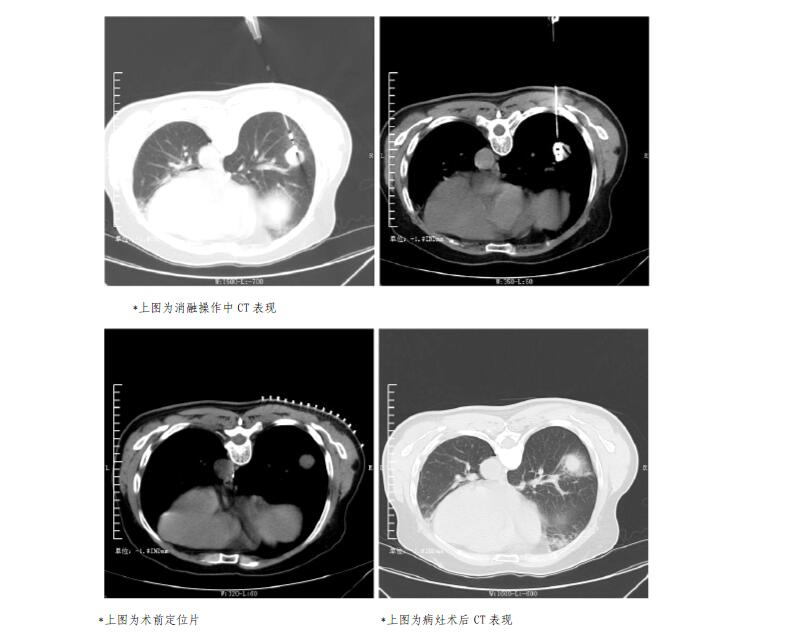

接下来让我们看一下患者的术中CT:

首次手术患者15天后复查的CT:肺内转移结节已被消融范围全面包裹,理论上包裹范围内肿瘤将全面失活(如下图)。